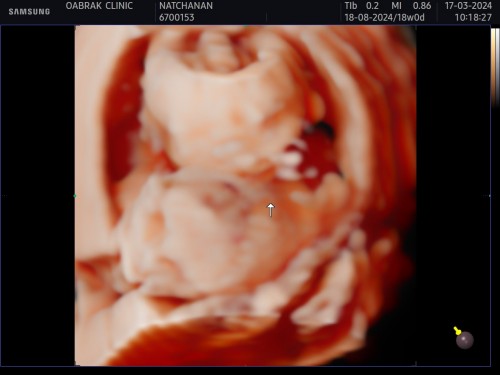

น้อง 18 วีคค่ะ ☺️ ยังเอเลี่ยนอยู่555